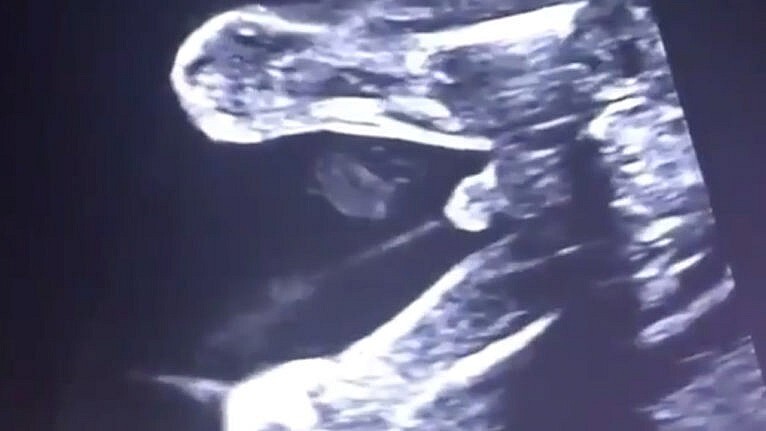

¿Sabías que el bebé orina dentro del útero? Su sistema urinario comienza a funcionar dentro del útero, y gracias a una ecografía podemos observar el preciso momento en el que un bebé hace pis dentro del útero.

Así orina el bebé dentro del útero

Ya sabemos cómo comienza a funcionar el sistema urinario del bebé dentro del útero, y como comentábamos al inicio, ahora podemos verlo con nuestros propios ojos gracias a una ecografía:

Vídeo | Dr. Ümit Korucuoğlu (reproducido con permiso expreso del autor)